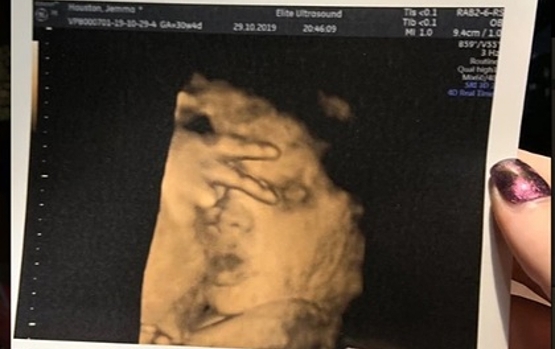

Нерожденный ребенок показал “знак победы“ на УЗИ и поразил врачей

Фото: Jemma Houston / Mirror Online

21-летняя Джемма Хьюстон из города Пейсли, Шотландия, рассказала, что ее будущий ребенок поразил врачей во время УЗИ, когда показал V-знак. Хьюстон отметила, что ее дочь никогда «не сотрудничает» во время ультразвуковых исследований и не ложится в правильное положение.

Беременная женщина сообщила, что это уже четвертое УЗИ, и что у нее нет ни одного нормального фото. Она добавила, что дочка будет «настоящей дивой», как и ее мать, и унаследует ее черты характера. Хьюстон посчитала жест ребенка смешным и сказала, что покажет это фото своей дочери в будущем.